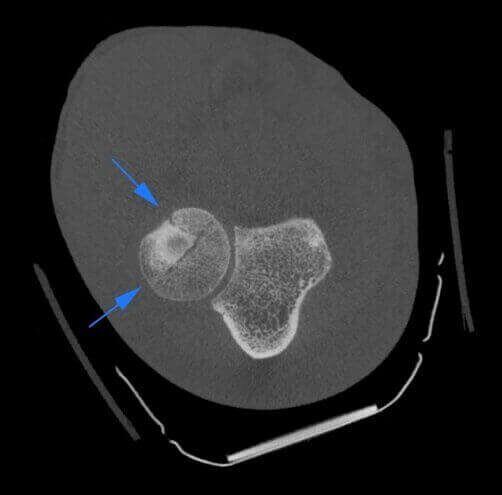

Fractura de la cabeza del radio en paciente con yeso.